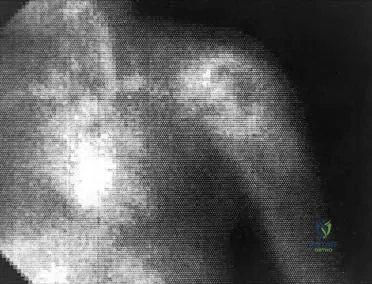

Question 33

View Answer & Explanation

Correct Answer: C

Rationale: The patient's age (adolescent), diaphyseal location, "onion-skin" periosteal reaction, large soft tissue component, and systemic symptoms (fever, weight loss) are classic features of Ewing sarcoma. Osteosarcoma typically presents in the metaphysis with a sunburst pattern. Chondrosarcoma is more common in older adults. Giant cell tumor is typically epiphyseal in young adults. Osteoid osteoma is a benign lesion with a characteristic nidus and pain relieved by NSAIDs, without systemic symptoms or a large soft tissue mass.